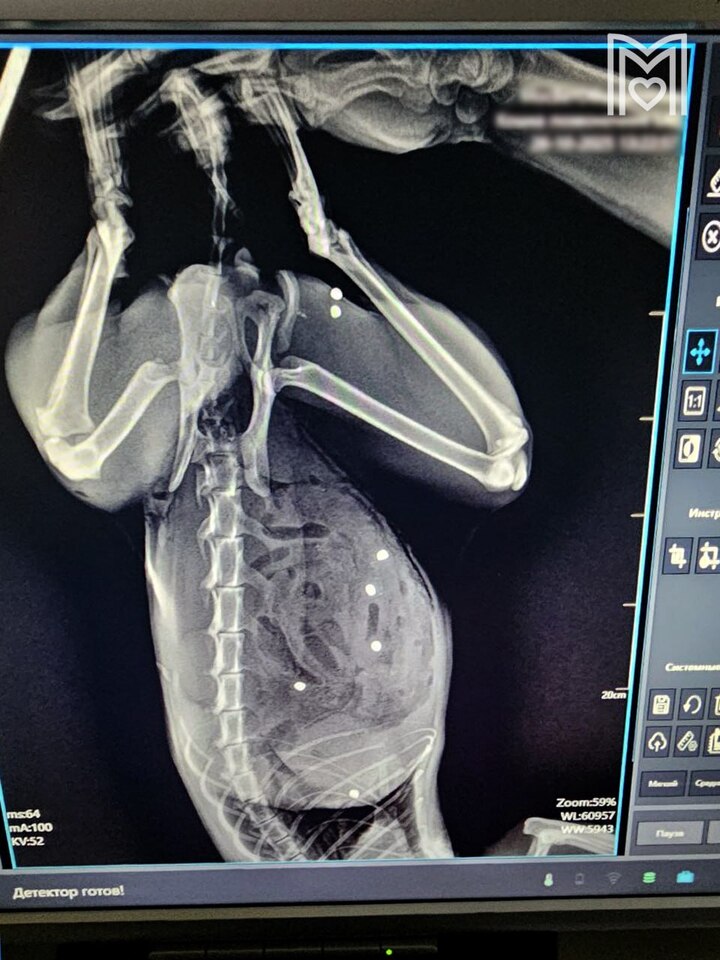

Выяснилось, что у животного пробит кишечник в 24 местах и в двух местах — селезенка. Так же пули попали в грудную клетку и мышцы бедра. Хирург немедленно приступил к операции, которая продлилась больше трех часов. В итоге почти безнадёжный пациент был спасён.